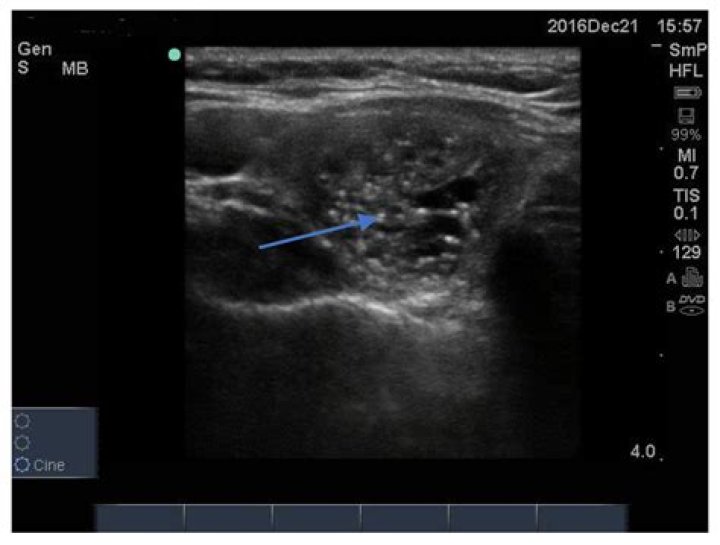

A malignant thyroid nodule tends to have ill-defined margins on ultrasound (Fig. 1). A peripheral halo of decreased echogenicity is seen around hypoechoic and isoechoic nodules and is caused by either the capsule of the nodule or compressed thyroid tissue and vessels [31].